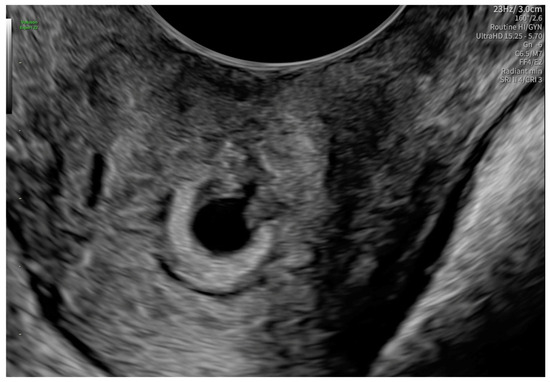

2. Case Presentation